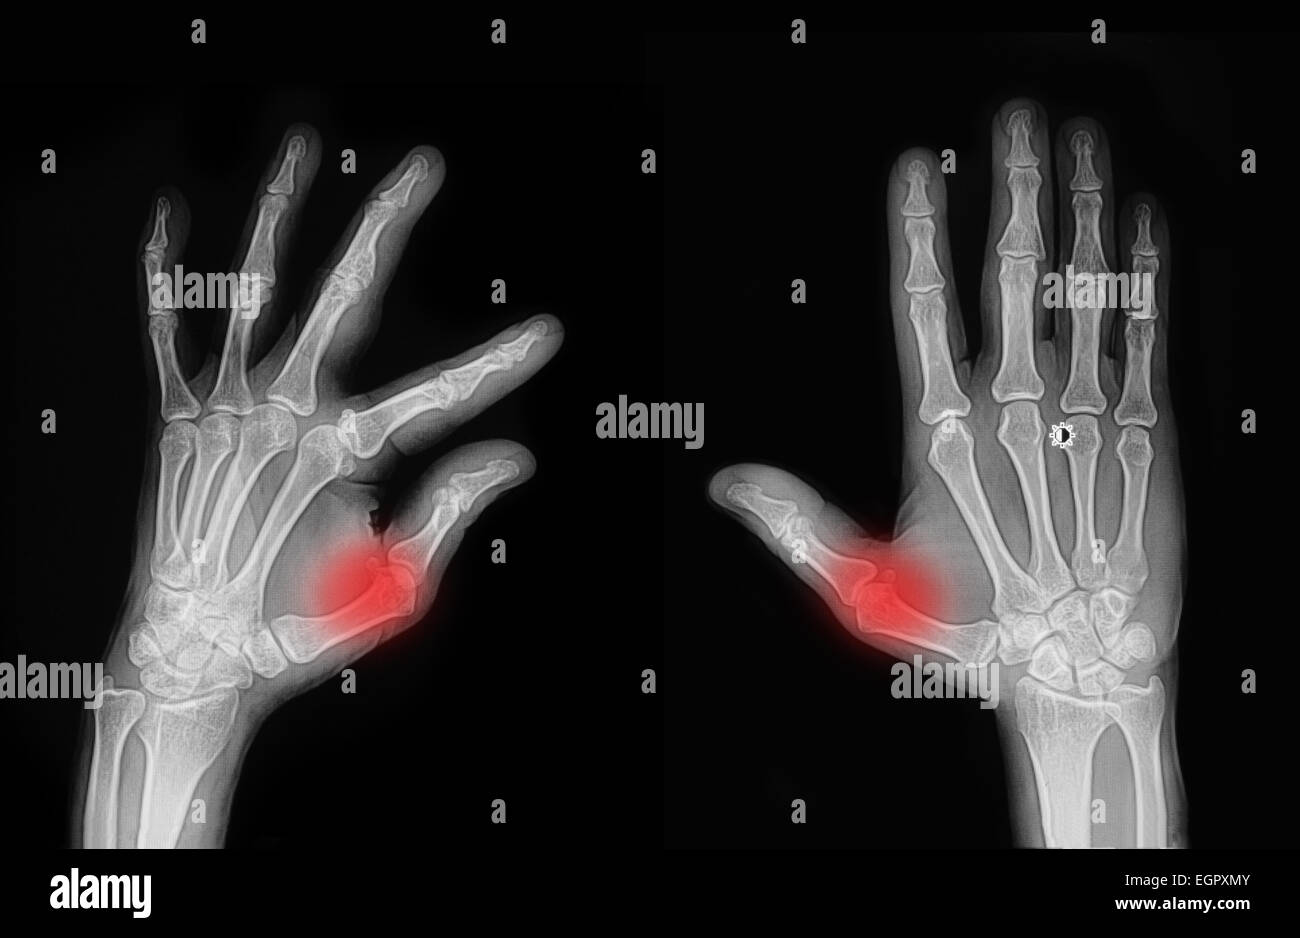

From www.shutterstock.com

Xray Image Both Hand Showing Index Stock Photo 331842149 Shutterstock Index Finger Fracture X Ray This article details the intricate anatomy of the hand as it relates to common finger injuries, illustrates the imaging findings of a range of injuries, presents optimal imaging. Your doctor will also look for injuries to other nearby structures. The hand comprises the metacarpal and phalangeal bones. This topic provides an overview of the initial evaluation, identification, and management of. Index Finger Fracture X Ray.